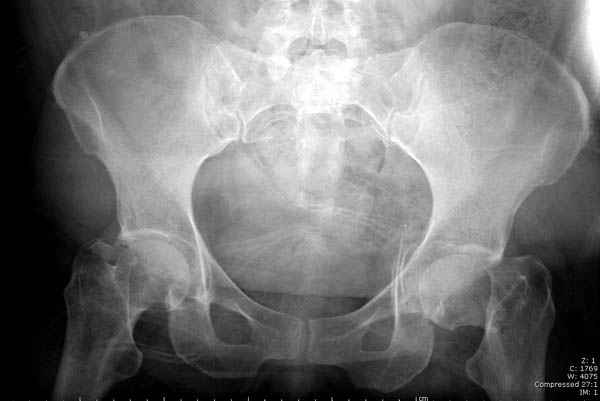

Уважаемые коллеги! С прошедшеми Вас праздниками. Теперь ближе к трудовым будням. Поступила 16 летняя девушка неделю назад. Механизм травмы падение с 5 этажа. Краткий диагноз:закрытый перелом левой ключицы, левого плеча, закрытый вертикально и ротационно нестабильный перелом костей таза:закрытый перелом левой подвздошной кости, переломы лонной кости справа, перелом обоих колонн вертлужной впадины слева;субкапитальный перелом шейки левой бедренной кости со смещением. По тактике лечения таза возникли следующие вопросы: 1. С чего начать - фиксации переломов вертлужной впадины или устранения деформаций таза? 2. Надо ли фиксировать шейку или фиксировать бедро в аппарате вместе с тазом, а после сращения таза планировать ТЭП ТБС? Если имеются еще какие подводные камни, будем рады выслушать.Спасибо.

У нас в таких случаях однозначно сделали бы остеосинтез Ш.Б. компрессирующими винтами, затем ЗВО таза, однозначно с дополнительной фиксацией в этом же аппарате бедра с разгрузкой тазобедренного сустава

В положении на спине подвздошным и надлобковым доступом восстанавливается тазовое кольцо, фиксация пластинами. При хорошей репозиции может улучшиться конгруэнтность в суставе.

Затем, если положение хорошее, закрытый остеосинтез шейки винтами.

Если нет - в положении на боку, синтез задней колонны из наружно-латерального доступа и синтез головки винтами, но уже под визуальным контролем.

Применение аппарата нецелесообразно, т.к. репозиция такого повреждения в аппарате крайне сложна и скорее приведет к удержанию имеющегося неправильного положения, а это надо?

На картинке подобный случай, только без шейки, сделано через месяц или полтора после травмы.